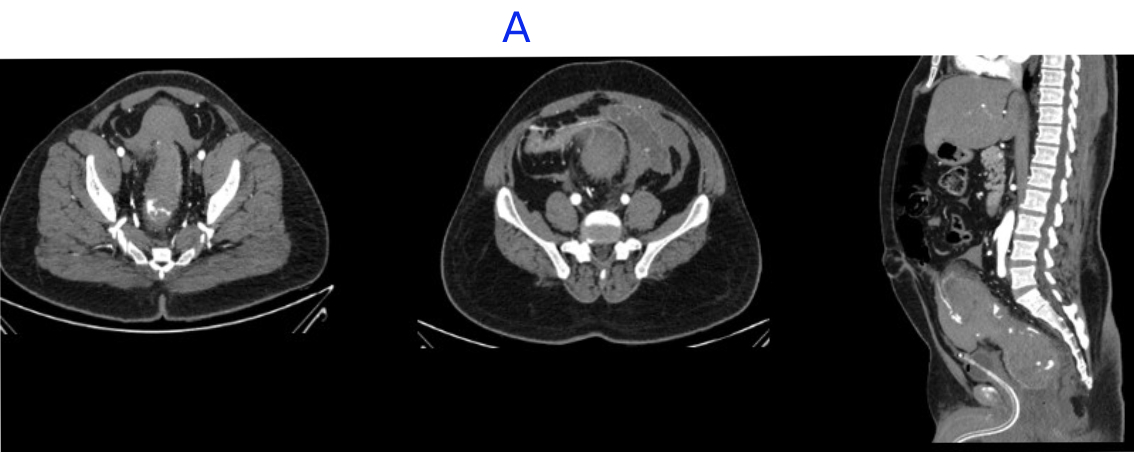

A. LEGENDS

- Large intramural hematoma with significant adjacnet fat starnding noted in rectum and distal sigmoid causing significant luminal narrowing.

- Multiple area of contrast extravasation within the hematoma which shows increase in size in venous and delayed phases with multiple pools of contrast - suggesting active bleeding from branches of inferior mesenteric artery..

- Distal rectum and proximal sigmoid colon mild edematous wall thickening.

- Hemorrhagic fluid noted in bilateral paracolic gutter and pelvis with active contrast extravasation.

- Omentomesenteric fat stranding in lower abdomen with mesorectal fascial thickening noted.